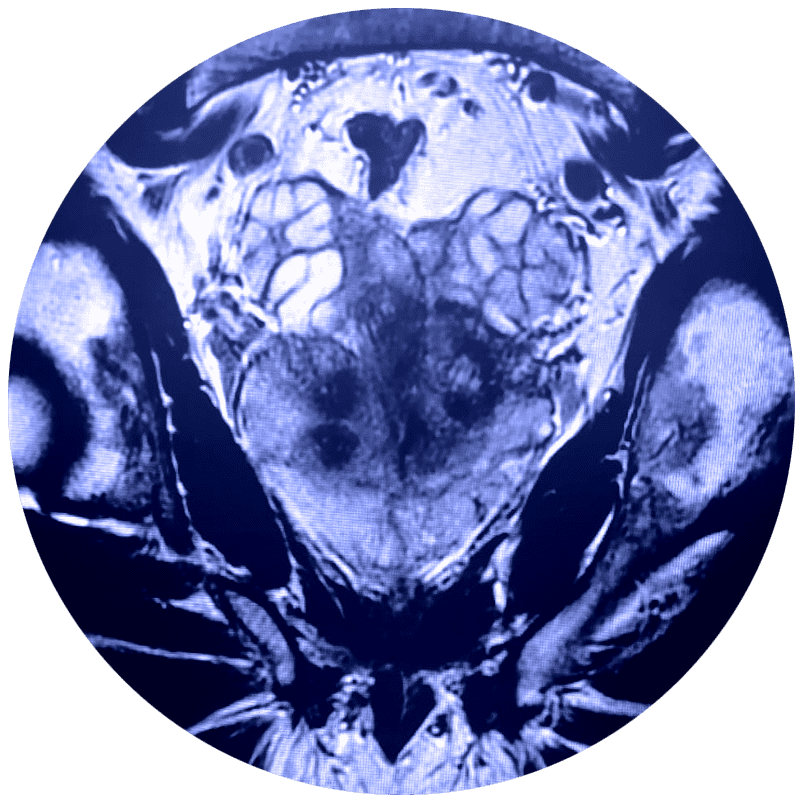

El estudio de Resonancia Multiparamétrica de Próstata no requiere de exposición a la radiación, evalúa el movimiento de las moléculas de agua (denominado difusión del agua) y el flujo sanguíneo (denominado imágenes de perfusión) adentro de la próstata. Esto ayuda al médico a diferenciar entre el tejido enfermo y el tejido sano de la próstata.

En estudio de Resonancia Multiparamétrica de Próstata tiene una sensibilidad diagnóstica de aproximadamente el 85% en los diferentes tipos de cáncer de próstata, especialmente aquellos que son significativamente agresivos. Además, cuenta con imágenes de alta resolución para lesiones o tumores pequeños.

Respecto al cáncer de próstata la Resonancia Magnética Multiparamétrica ha adquirido en los últimos años un papel importante, tanto en el diagnóstico en caso de elevación del PSA (antígeno prostático específico en sangre) con biopsias negativas, como en la estadificación local y a distancia, e incluso en la monitorización del tratamiento.

El médico utiliza la RMN para evaluar el cáncer de próstata y ver si se encuentra confinado a la próstata. La Mp-MRI proporciona información acerca de las moléculas de agua y del flujo sanguíneo a través de la próstata. Esto ayuda a determinar si el cáncer se encuentra presente y, si es el caso, si es agresivo y si se ha diseminado.